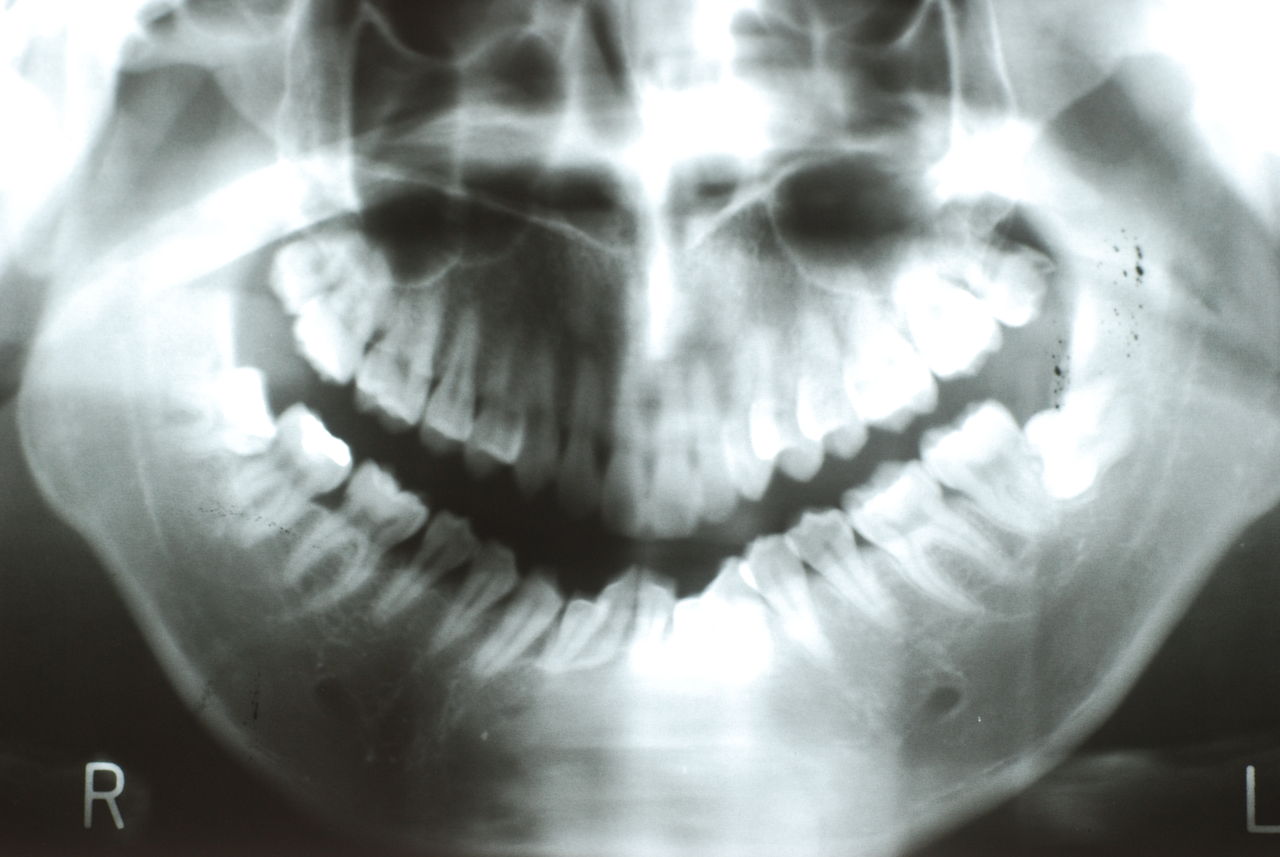

下顎の親知らずが左右とも横向きです。

横向きに生えてくる頻度 下顎の親知らずは生えるスペースがなく横向きに生えてくる頻度が、上顎に比べ高いです。

でも、レントゲン写真を撮ってみたら、骨の中に埋まっている親知らず袋状の病変ができていることがあります。

歯根が長くなると、下顎管と親知らずの距離が近くなってしまい、抜歯の難易度が上がり、同時に、神経を麻痺させてしまうリスクも上がってしまいます。